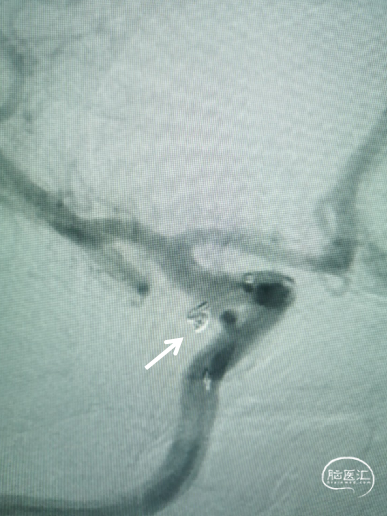

2、右侧后交通动脉瘤介入栓塞治疗:路图指引,6F 导引导管到位右侧C1段末端, XT-17支架导管、Echelon-10微导管预塑“C”形,在Synchro-14微导丝引导下先后到位,栓塞微导管到位十分顺利, 推入1枚Target Nano 1.5mm*3cm弹簧圈后,经支架导管送入1枚4.5mm*21mm Atlas支架保护瘤颈,顺利到位并释放,对栓塞微导管完全无影响, 解脱弹簧圈后再推入1枚1mm*2cm弹簧圈,顺利推入,解脱后造影显示支架打开良好,弹簧圈稳定,动脉瘤不显影。

送入1枚4.5mm*21mm Atlas支架,顺利到位并释放,微导管稳定,完全送入首枚弹簧圈顺利,无踢管现象。

支架打开良好,微导管稳定,再送入1枚1mm*2cm弹簧圈 ,无踢管现象。

术后即刻造影:弹簧圈稳定、支架打开良好、动脉瘤致密栓塞,Raymond 1级。